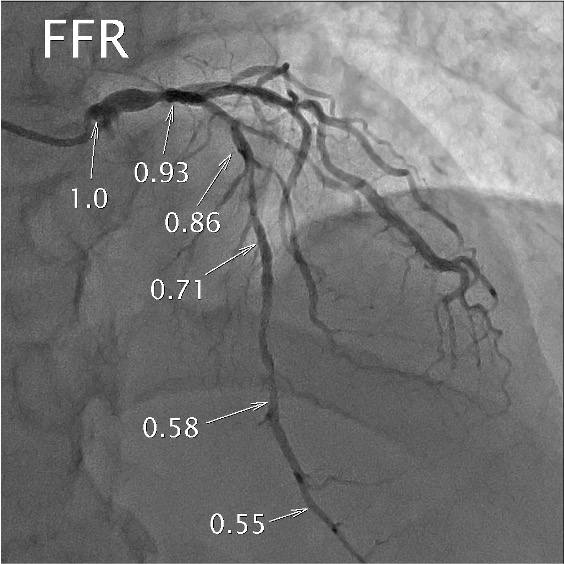

- FFR LAD 0.55, LCx 0.69, RCA 0.58

LAD FFR & Dx RFR